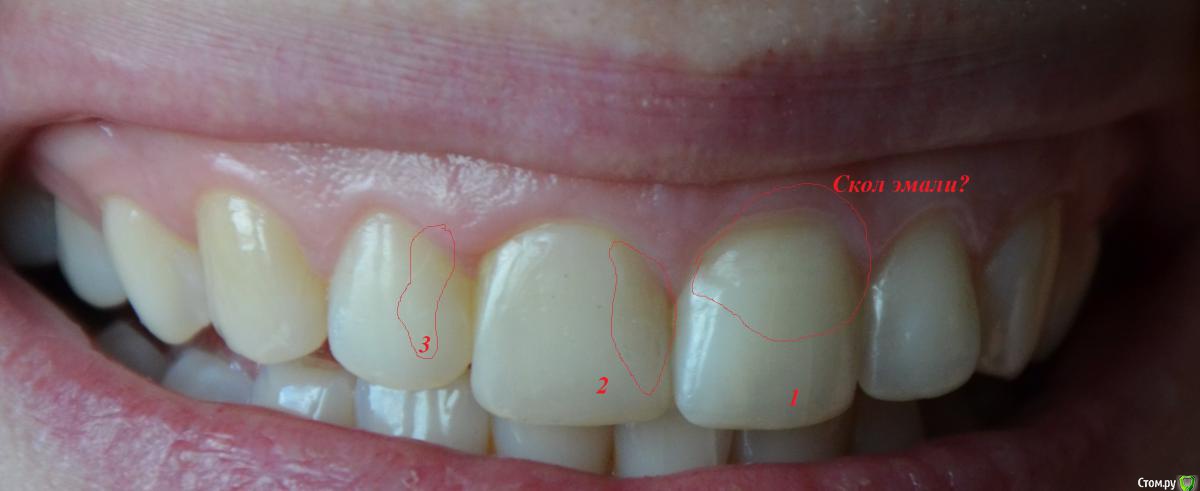

Olga82 Опубликовано 24 апреля, 2015 Поделиться Опубликовано 24 апреля, 2015 Прошу совета в нижеследующих проблемах:Зубы начала лечить с января 2105 года(Рентген-снимок именно до лечения прилагается), вылечила уже все зубы кроме одного(26-й или 16-й, не знаю, с какой стороны правильно вести отсчет).Проблема №1:Сделали верхние передние(замена пломбы+выравнивание режующей поверхности посредством пломб на обоих зубах+полировка(шлифовка).После шлифовки появились сначала белый точки, потом на зубе 1(фото прилагается) при чистке зубов прямо отошел тонкий кусочек как пленка полупрозначная зуба(зуб вообще был здоровый, только неровный рез), теперь там выемка как бы вглубь), на зубе 2 сейчас неровная как неотшлифованная поверхность (на фото, к сожалению, плохо видно, невозможно снять), на зубе 3 идет полоса на эмали-опять-таки как дефект шлифовки.Как это понимать? Топорная шлифовка или мои проблемы с зубами? дело в том, что я кормлю грудью уже 2 года, мой стоматолог сказал, что в зубах судя по всему мало кальция, поскольку после несильной заморозки один из них быстро побелел.Что мне предпринять? Дошлифовать недошлифованное?Или не трогать, а провести реминерализацию/глубокое фторирование/пропить курс витаминов и только потом их трогать? Какова судьба моих любимых передних зубов-печальная или смотреть оптимистично? Проблема №2:Дней пять как стали ныть нижние зубы(по фото обвела), их не лечили, они вроде как здоровые, небольшой коричневый налет присутствует с внутреннего края на одном, стоматолог его немного поскреб ....и смолчал...ничего не сказал...это камень, я правильно понимаю?Боль постоянная, тупообразная.Я полна мыслей об отстутствии кальция в моих зубах и слабости эмали купила пасту Лакалют сенситив, чищу ей второй день-пока нет результата, как болело, так и болит, полощу ротовую полость содой.Что это может быть?К стоматологу записана на 3 мая, не знаю, доживу ли до этого срока.Надо срочно бежать ?Спасибо всем за уделенное время моим проблемам. Ссылка на комментарий

Olga82 Опубликовано 25 апреля, 2015 Автор Поделиться Опубликовано 25 апреля, 2015 Вас сюда на задание Шон Коннер отправил? Да все что не дополировано, дополировать А у меня зубы не начнут сыпаться-откалываться? Меня пугает, что на каждом полированном белые точки появились(возможно это воздух?), и что произошел скол эмали с №1.До полировок с зубами подобного не происходило.так можно дополироваться до постановки виниров(Нет? В чем может быть причина ноющей боли в нижних передних? Как мне можно её снять до визита к врачу?(несколько дней).Это болезнь десен или чувствительность зубов по большей вероятности? Ссылка на комментарий

Olga82 Опубликовано 25 апреля, 2015 Автор Поделиться Опубликовано 25 апреля, 2015 все что недоудолено- доудалить(1.8, 2.8, 3.8) Это чёй-то? У меня показания к удалению только одного зуба(я с номерами уже запуталась, он наверху). все что недобрекетированно-добрекетировать Это зачем это? Всё так плохо что ли? Ну не идеально ровно, согласна....но мне как-то всё-равно, особо не заметно ни мне, ни окружающим нестоматологам.Мой врач сказал, что прикус нормальный, без претензий на идеальность, но жить можно без ущерба здоровью зубов.Вы считаете, что в этом есть обязательная необходимость?В мои то года? еще и допротезировать(2.6, 4.6, 4.7) Остальное все уже сделано, запломбировано и запротезировано.Снимок январский....после чего раз в неделю как на работу уже ухожу..... вопрос не по теме: почему кормите 2 года?О_о Я не сумасшедший фанат долгого кормления, так сложилось в силу объективных причин согласованных с педиатором.Планирую завернуть через пару месяцев. Скажите мне, пожалуйста, отчего могут быть сколы эмали на зубах после полировки и белые точки? Ссылка на комментарий

faity Опубликовано 25 апреля, 2015 Поделиться Опубликовано 25 апреля, 2015 я написал офигительно длинный пост и случайно все удалил(((поэтому вкратце: отчего могут быть сколы эмали на зубах после полировки и белые точки? сколы из-за неправильного распределения нагрузки во время жевания, неправильное распределения нагрузки- из-за неправильного прикуса, пятна либо недополировали, либо после полировки покрыли адгезивом, чтобы "блястело сразу в кресле" Это чёй-то? У меня показания к удалению только одного зуба(я с номерами уже запуталась, он наверху). показания ортодонтические .Мой врач сказал, что прикус нормальный, без претензий на идеальность, но жить можно без ущерба здоровью зубов.Вы считаете, что в этом есть обязательная необходимость? Прикус патологический и если эстетика вас не напрягает, то артрит височно-нижнечелюстного сустава начнет рано или поздно давать о себе знать. Плюс читайте выше про ударные нагрузки и к чему это приводит. Ссылка на комментарий